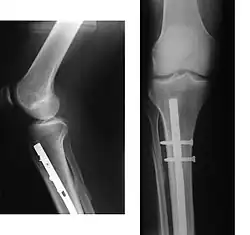

Radiography to identify possible fractures after a knee injury

A bone fracture may be diagnosed based on the history given and the physical examination performed. Radiographic imaging is often performed to confirm the diagnosis. Under certain circumstances, radiographic examination of the nearby joints is indicated to exclude dislocations and fracture-dislocations. In situations where projectional radiography alone is insufficient, Computed Tomography (CT) or Magnetic Resonance Imaging (MRI) may be indicated.

X-ray showing the proximal portion of a fractured tibia with an intramedullary nail